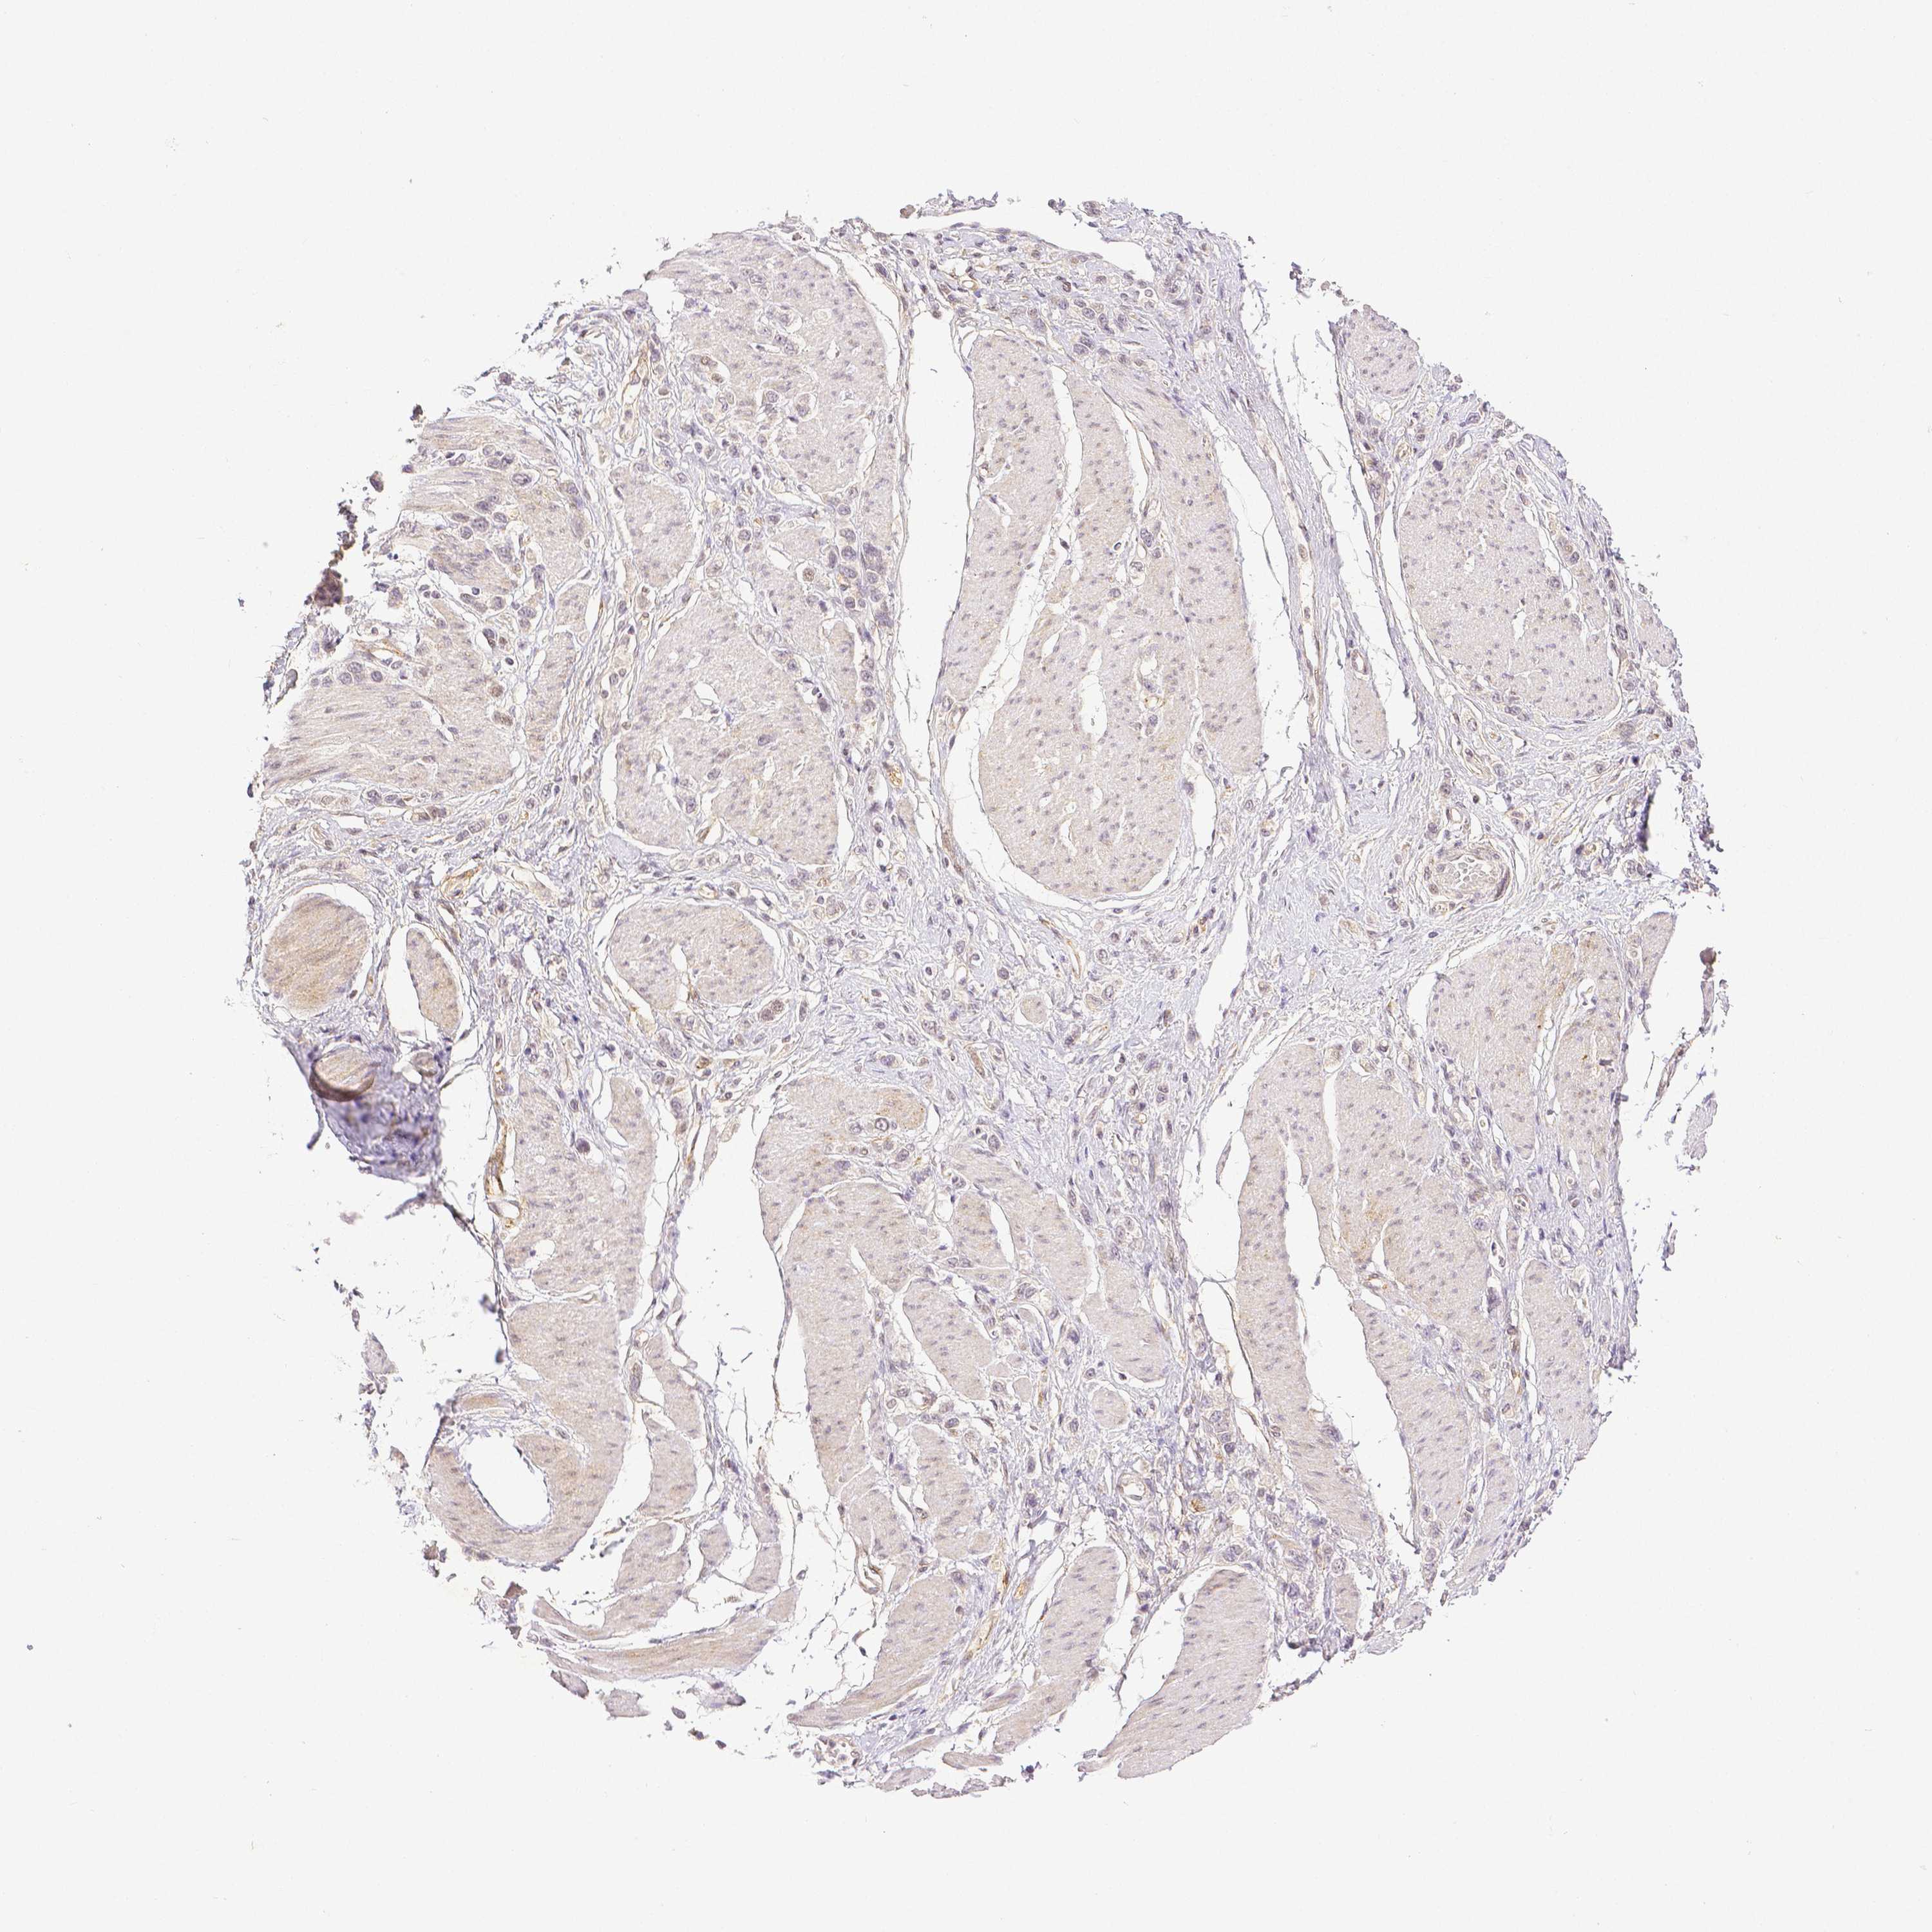

STOMACH CANCER - Protein expressioni

A mouse-over function shows sample information and annotation data. Click on an image to view it in a full screen mode. Samples can be filtered based on level of antibody staining by selecting one or several of the following categories: high, medium, low and not detected. The assay and annotation is described here.

Antibody stainingi

Antibody staining in the annotated cell types in the current human tissue is reported as not detected, low, medium, or high, based on conventional immunohistochemistry profiling in selected tissues. This score is based on the combination of the staining intensity and fraction of stained cells.

Each image is clickable and will lead to virtual microscopy that enables deeper exploration of all samples and also displays staining intensity scores, fraction scores and subcellular localization as well as patient and tissue information for each sample.

Antibody HPA003733

Antibody CAB068243

Antibody CAB068244

Staining

High

Medium

Low

Not detected

Intensity

Strong

Moderate

Weak

Negative

Quantity

>75%

75%-25%

<25%

None

Location

Nuclear

Cytoplasmic/membranous

Cytoplasmic/membranous,nuclear

Adenocarcinoma, NOS